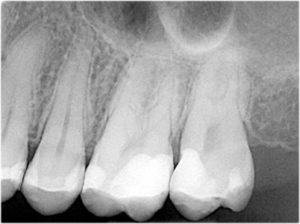

Detection of MB2 canal in maxillary first molar using radiographic ...

Examples of isthmuses between the mesiobuccal canal(MB)1 and MB2 root ...

A) Consecutive slices showing an II pattern in a filled MB2 canal. B ...